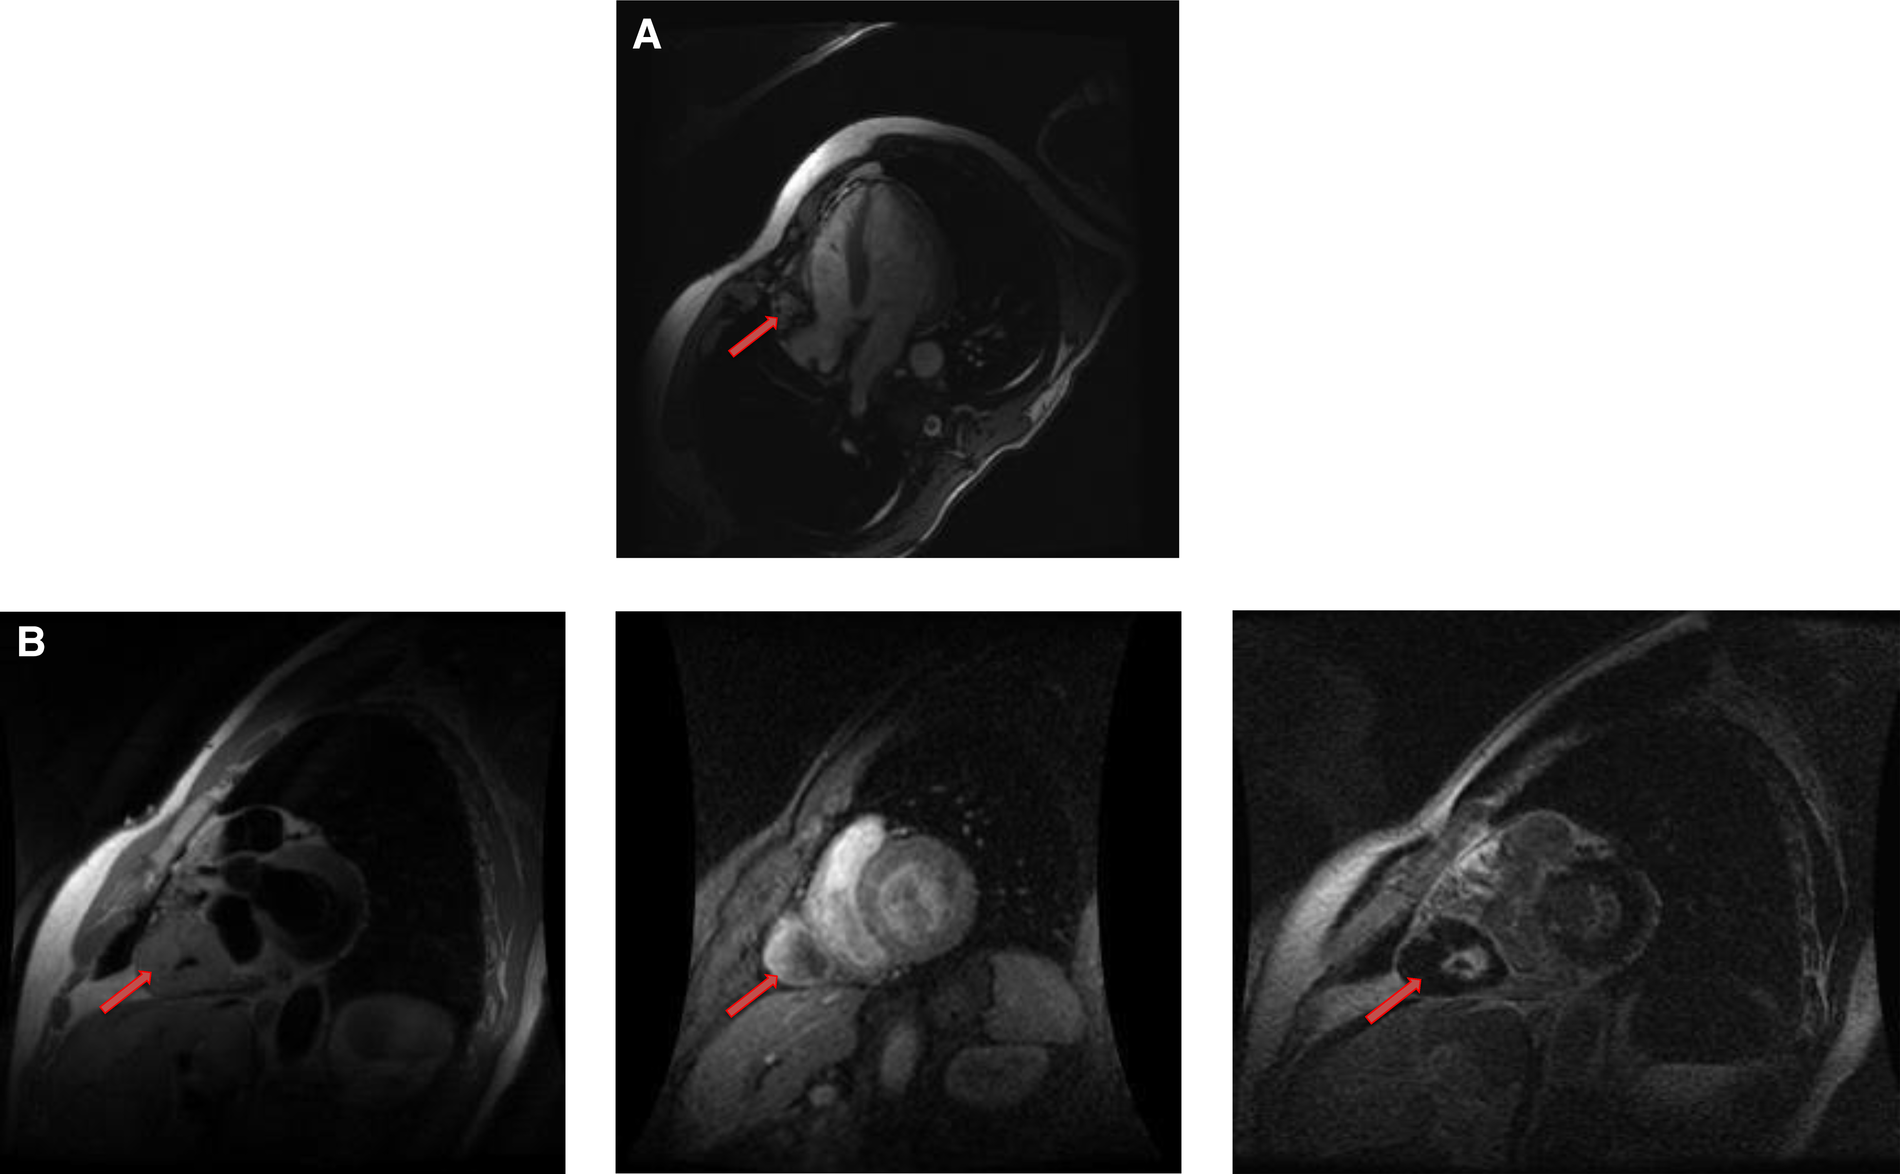

4.5.1. Cardiac MRI features

Fibromas are of variable signal intensity on SSFP cine images. As compared to the myocardium, they are usually isointense on T1-weighted images and are characteristically hypointense on T2-weighted images (50). Although, they are generally homogeneous in appearance, a patchy, central hypo intensity may be seen due to central calcification, which gives them a heterogeneous appearance.

They are avascular in nature and do not show contrast enhancement during perfusion imaging. Characteristically, they show intense hyper-enhancement on LGE images. The potential explanation of this intense LGE pattern is that microscopically they are composed of collagen and fibroblasts; therefore, they have a very large extracellular space content. Gadolinium diffuses into interstitial spaces and results in a delayed and persistent concentration of gadolinium contrast agent (Table 1 and Figure 10).

Rhabdomyomas are typically homogeneous in appearance on CMR and are hypointense to the myocardium on SSFP cine sequences. They appear isointense/hypointense on T1 Weighted images and slightly hyperintense on T2-weighted images (Figure 10). On LGE images, they usually show very minimal or no enhancement after the injection of contrast material (Table 1).

Figure 10

A 31-year-old male with left ventricular fibroma. (A) This mass demonstrates no perfusion on first-pass imaging (red arrow, short axis view). (B–F) Homogeneous intense enhancement of the mass is noted on late gadolinium enhanced images (red arrows, 3chamber and short axis views).

Cardiac paragangliomas are rare hyper-vascular masses that arise from the cardiac neuroendocrine cells (55). Patients are usually young and present with various symptoms of excessive catecholamine secretion. Surgical resection is often recommended, although it is challenging presumably due to their vascular nature and intimate relationship with the coronary arteries. On CMR, they are isointense to the myocardium on T1-weighted images and significantly hyperintense on T2 -weighted images (56). Due to high vascularity, they typically show uniform, intense enhancement during and after gadolinium contrast administration (Figures 11,12). Occasionally, they may show heterogeneous enhancement due to associated areas of hemorrhage and necrosis.

Figure 11

A 54-year-old male with right ventricular pheochromocytoma. (A) The mass is isointense on T1- weighted, dark blood, double inversion recovery fast spin echo images (red arrow). (B) The mass demonstrates peripheral hyper-vascularity with central areas of nonenhancement on first pass perfusion images (red arrow). (C) There is central enhancement of this mass on late gadolinium enhanced images (red arrow).

Figure 12

A 53-year-old male with inter-atrial septal pheochromocytoma. (A) The mass is bright on T2- weighted, dark blood, double inversion recovery fast spin echo images (red arrow). (B) This mass shows heterogeneous enhancement on late gadolinium enhanced images (red arrow).